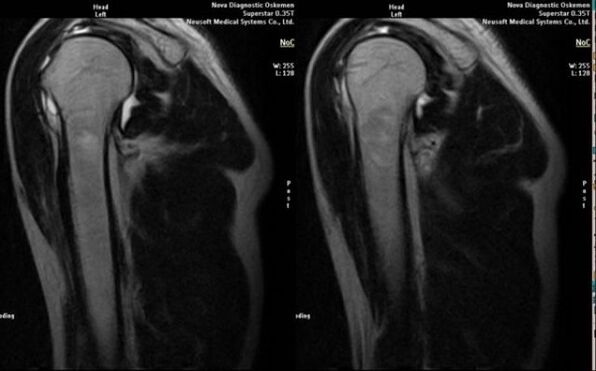

- magnetic resonance and computer tomography;

Signs that indicate the development of arthrosis directly include the appearance of a significant narrowing of the joint space, sclerosis of subcartilaginous structures, thinning of the chondrocyte layer itself, the appearance of osteophytes and the deposition of salt crystals in the intra-articular fluid.